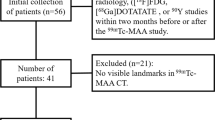

SPECT/CT: dataset 4

Dataset 4 was used to evaluate the impact of automated segmentation on dosimetry outcome. The dataset consisted of images from 8 patients with neuroendocrine tumours treated with 1 cycle of 177Lu-DOTATOC (7.5 GBq/cycle) undergoing kidney dosimetry in the context of a clinical study (internal). Abdominal contrast-enhanced CT scans were used to determine the volume of both kidneys. Four (4) abdominal SPECT/CT scans with in-plane SPECT image size of \(256 \times 256\) and Low-Dose CT (LDCT) scans with an in-plane size of \(512 \times 512\) were acquired at 0.5 h, 6 h, 24 h, 72 h post injection (p.i.). Co-registration between the LDCT scans and the SPECT scans was verified by two separate medical imaging experts, and the images were further coregistered manually when needed.